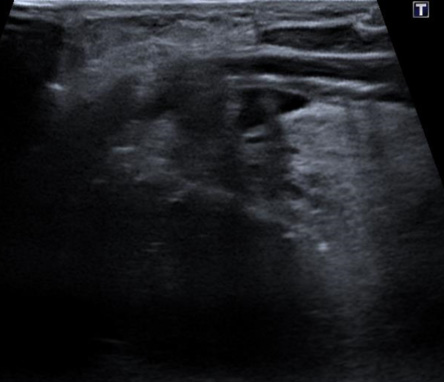

La radiofréquence percutanée des nodules thyroïdiens est une technique d'ablation mini-invasive guidée par échographie : une électrode fine introduite dans le nodule le détruit par la chaleur, sans incision, sans cicatrice, sous anesthésie locale, en ambulatoire. Alternative à la chirurgie thyroïdienne (thyroïdectomie) pour les nodules bénins symptomatiques.

Il s'agit de détruire partiellement ou totalement un nodule thyroïdien bénin par la chaleur produite par une aiguille de radiofréquence, introduite par voie percutanée sous guidage échographique, sans chirurgie. Le courant de radiofréquence chauffe le tissu du nodule jusqu'à environ 60–80°C, détruisant les cellules ciblées tout en préservant le tissu thyroïdien sain environnant.

Introduction de l'électrode de radiofréquence dans le nodule sous guidage échographique en temps réel

La radiofréquence (RF) est une technique d'ablation thermique qui utilise des ondes électromagnétiques pour chauffer et détruire le tissu nodulaire depuis l'intérieur, sous guidage échographique en temps réel. Une fine électrode est introduite dans le nodule à traiter. Aucune cicatrice, aucune anesthésie générale.